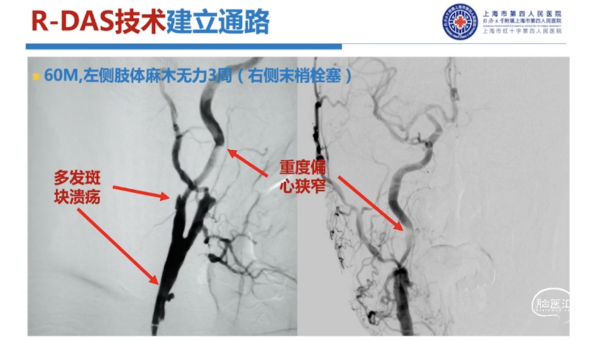

如下图病例所示,我们首先用R-DAS技术通过Sim II导管进行降主动脉成形,超选左侧颈总动脉,导丝到位,然后将银蛇DA远端通路导引导管放置到位,其到位后,后面的操作就至关重要,此时使用内部交换技术,将0.035"导丝保留在体内,将造影导管撤出。此时里边仍然有根0.035"导丝,然后再置入一根0.018"的加硬导丝,放置到位。0.018"导丝头端到达银蛇DA远端通路导引导管的头端,这个时候再撤出0.035"导丝,在整个过程中,银蛇DA远端通路导引导管内部一直有一根导丝在支撑,就可以完全避免导管打折。